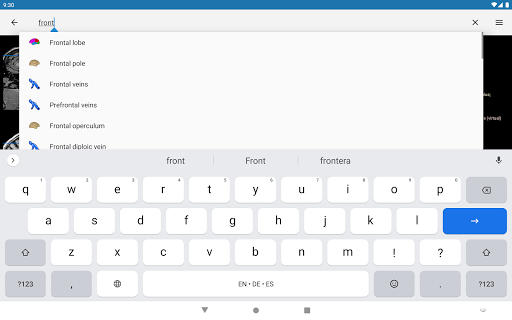

- Mudah menemukan struktur anatomi berkat pencarian indeks

*Meningkatkan kinerja pencarian struktur anatomi

*Temukan bagian anatomi Anda dengan lebih mudah berkat fitur pencarian baru yang lebih intuitif dan canggih